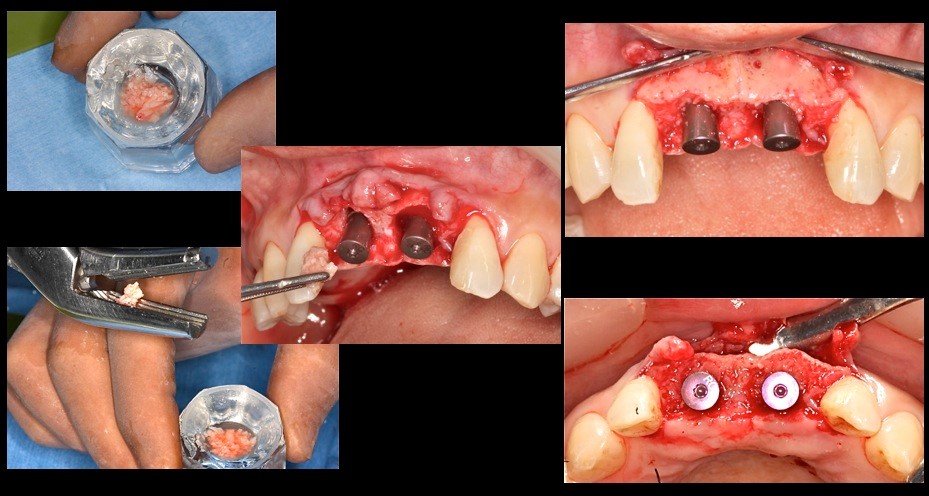

上顎中切歯 抜歯即時のケース

上顎前歯部フライスドリルで形成(直径3.5㎜)埋入インプラントは10㎜の計画であるがフライスドリルでは14㎜まで骨採取のために形成する 深度ゲージで深度確認 形成部位に骨尖を確認することができる(左上1)(右上1はすでに骨採取後)

クリッケラー先生考案の骨採取の鉗子にて骨尖採取

インプラント埋入 抜歯窩とインプラントに空隙があることがわかる

この部位に中切歯2本分の骨尖を砕いて隙間に填塞する 右下の写真で十分填塞できていることが確認できる。